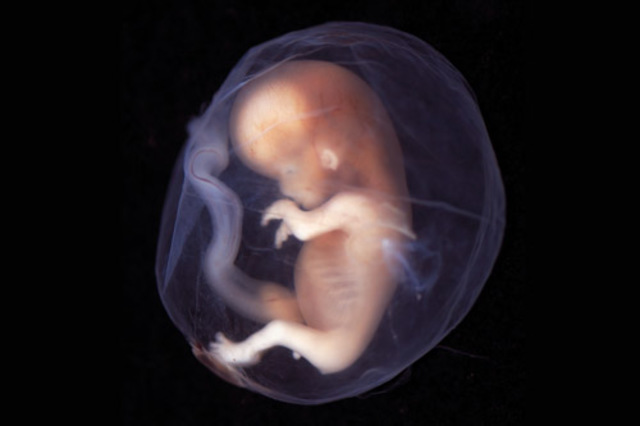

Etapa prenatal

Desde la concepción hasta el nacimiento.

• Estado embrionario

Estado embrionario

La mórula ha acabado su viaje a través de la trompa de Falopio y alcanza el interior del útero. Comienza una nueva transformación celular en la que las células se dividen en dos grupos. Uno de ellos comienza a formar el blastoembrión, que es lo que será el futuro embrión. El otro grupo de células van a componer lo que se denomina trofoblasto, que es la capa que va a proteger el embrión y a su vez le va a ayudar a implantarse en el endometrio.

• Preparación para el embarazo

Preparación para el embarazo

El trofoblasto segrega una serie de encimas que provocan que el endometrio sea más receptivo. El blastocito puede entonces comenzar la anidación agarrándose a las paredes del útero. El endometrio comienza a segregar la hormona hCG. Por efecto de esta hormona, el cuerpo lúteo no suspende la producción de progesterona. Es por eso que el ciclo menstrual se interrumpe y la matriz comienza a prepararse para el embarazo.

• 2da. Semana

2da. Semana

Comienza la formación del saco amniótico. El embrión crece hasta alcanzar 1,5 milímetros. el futuro embrión está formado por dos esferas huecas, una ubicada en el interior de la otra. La externa y más voluminosa, se llama saco coriónico. La interna incluye al llamado disco embrionario, el cual está formado por dos capas de tejido, por esto se lo denomina disco embrionario bilaminar.